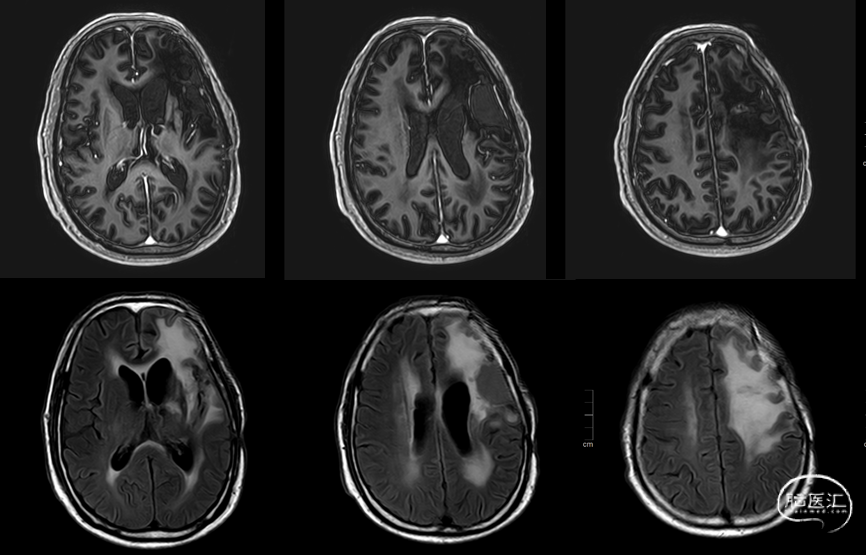

术后48小时MR,可见左额不规则混杂信号影,周围水肿:图示。

术后48小时MR,增强后边缘不规则线样强化,靠近放射冠及侧脑室壁可疑少许残存:图示。

入院前头MRI(2020-3):左侧额岛叶肿块,信号不均匀,其内可见出血和坏死,占位效应明显,周围见水肿。考虑左额岛叶肿瘤(高级别脑胶质瘤可能性大)。于2020年4月行左额岛叶占位性病变切除术。术中见肿瘤组织位于左侧额中回及额下回后部,大小约4m×5cm×5cm,呈烂鱼肉样,色灰红,质软,部分坏死,血运中等,边界不清,侵犯左侧岛叶向下挤压颞叶。显微镜下沿肿瘤周边胶质增生带完整切除肿瘤。术后48小时内复查头MRI平扫、加强,影像显示术腔边缘不规则线样强化,靠近放射冠及侧脑室壁强化明显,可疑少许残存。

术后组织学诊断:高级别胶质瘤,WHO 4级;分子病理:IDH1 R132H野生型,1p19q 1p/19q未缺失,TERT C250T突变,BRAF V600E 无突变,MGMT启动子甲基化未检测到。整合诊断:胶质母细胞瘤(WHO 4级 IDH野生型)。

这是一个对中老年GBM患者治疗的一个非常标准和完整的一个方案,此病例中患者的无进展生存已达25个月,获益是显而易见的。术前影像评估提示一个左侧额中下回、岛叶的胶质瘤,范围较广,涉及到语言功能区,并已有命名性失语,该区域不建议做扩大切除,故沿肿瘤边缘脑沟入路分离到白质下做了近全切除,近放射冠侧脑室壁处残余少许,手术的目的已达到,肿瘤充分减容、保留功能及获取病理,术后48小时MR已证实了切除程度。术后病理及整合诊断考虑为GBM WHO 4级,分子病理MGMT启动子非甲基化、TERT突变;术后经MDT会诊,依据共识和指南给予患者同步放化疗及替莫唑胺的序贯治疗,同步放化疗1个月后加用TTFields辅助治疗,患者的依从性良好,仅有也是常见的副反应是头皮局部的反应。经过2年多的治疗病情一直比较稳定,影像上也可见原瘤腔残余肿瘤历经水肿、假性进展阶段并逐渐的消弥,目前在MR PWI已呈低灌注表现,影像上未见有新发病灶,治疗效果总体令人满意。TTFields的疗效呈时间依赖性,预期生存6个月以上的患者才能更显出TTFields的作用。该患者为老年男性,手术切除较彻底,影像学显示仅在术腔内侧近中线处可疑少量残留。术后病理为胶质母细胞瘤,诊断明确,分子病理示IDH野生型,MGMT启动子无甲基化,TERT基因突变,预后最差的分子亚型。